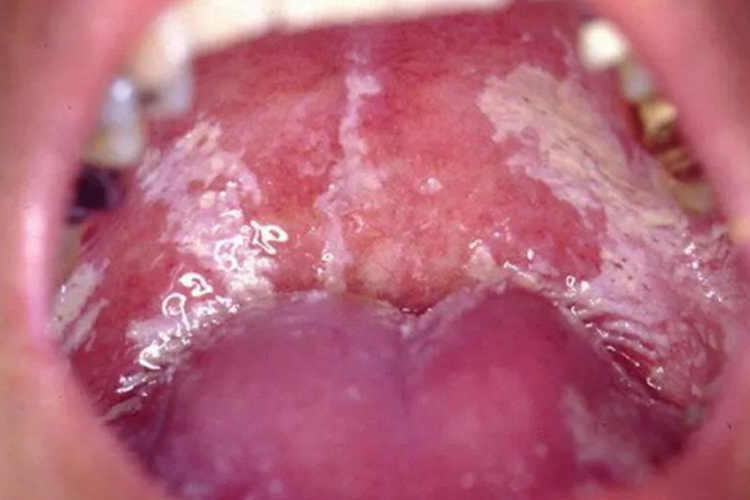

急性假膜型念珠菌病:病损可发生于口腔黏膜的任何部位,表现为口腔黏膜上出现乳白色绒状膜,为白色念珠菌的菌丝及坏死脱落的上皮汇集而成。轻时病变周围的黏膜无明显变化,重时则四周黏膜充血发红。患者自觉症状为口干、烧灼不适、轻微疼痛。

慢性增殖性念珠菌病:临床表现为黏膜上有白色斑块,为白斑样增生及角化病变,黏膜上亦间断有红色斑块。严重时白斑表面有颗粒增生,黏膜失去弹性,自觉症状为口干、烧灼感及轻微疼痛。